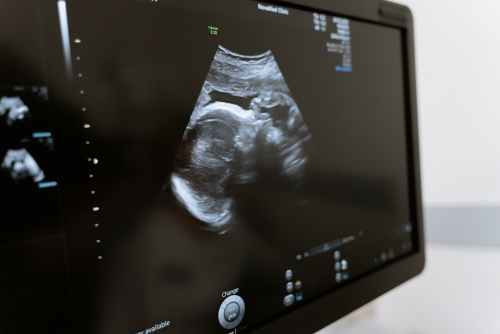

腹部血管超聲檢查比較簡(jiǎn)單,一般當(dāng)患者出現(xiàn)腹痛、腹脹、惡心、嘔吐等癥狀時(shí),可通過超聲檢查,判斷腹腔內(nèi)血管是否出現(xiàn)病變。臨床上腹部血管超聲檢查的常見情況,包括腹主動(dòng)脈瘤、下腔靜脈血栓、門靜脈主干內(nèi)徑測(cè)量、肝靜脈內(nèi)徑測(cè)量等。

1、腹主動(dòng)脈瘤:是腹部血管常見的疾病,可通過腹部血管超聲檢查,發(fā)現(xiàn)腹主動(dòng)脈處直徑超過4.5cm的動(dòng)脈瘤,還可觀察到瘤體內(nèi)有無(wú)附壁血栓,以及瘤體與周圍血管的比例。如果出現(xiàn)腹主動(dòng)脈瘤,還需觀察腹主動(dòng)脈的起始段是否有斑塊形成;

2、下腔靜脈血栓:也是常見的腹部血管疾病,可通過下腔靜脈超聲檢查,發(fā)現(xiàn)下腔靜脈內(nèi)徑測(cè)量增寬,如果有血栓,還可觀察到血栓部位、范圍,以及側(cè)支循環(huán)情況。如果出現(xiàn)下腔靜脈血栓,還需觀察下腔靜脈回流情況;

3、門靜脈主干內(nèi)徑測(cè)量:該檢查可觀察到門靜脈主干內(nèi)徑測(cè)量的具體情況,明確是否有門靜脈高壓的情況。如果門靜脈主干內(nèi)徑大于1.5cm,提示存在門靜脈高壓,需及時(shí)進(jìn)行相應(yīng)治療;

4、肝靜脈內(nèi)徑測(cè)量:肝靜脈內(nèi)徑測(cè)量可以觀察到是否存在肝靜脈變異情況,正常人肝靜脈內(nèi)徑在10mm左右。如果測(cè)量肝靜脈內(nèi)徑大于1.5cm,提示存在肝靜脈變異,有肝靜脈堵塞的可能。

除上述檢查外,進(jìn)行腹部血管超聲檢查時(shí),還可觀察到靜脈瓣膜結(jié)構(gòu)和功能是否正常。因?yàn)槌暀z查具有無(wú)創(chuàng)性,所以可用于多數(shù)情況下的首選。如果患者經(jīng)過超聲檢查,發(fā)現(xiàn)存在異常情況,建議及時(shí)進(jìn)行增強(qiáng)CT或核磁共振等其他影像學(xué)檢查以明確診斷。